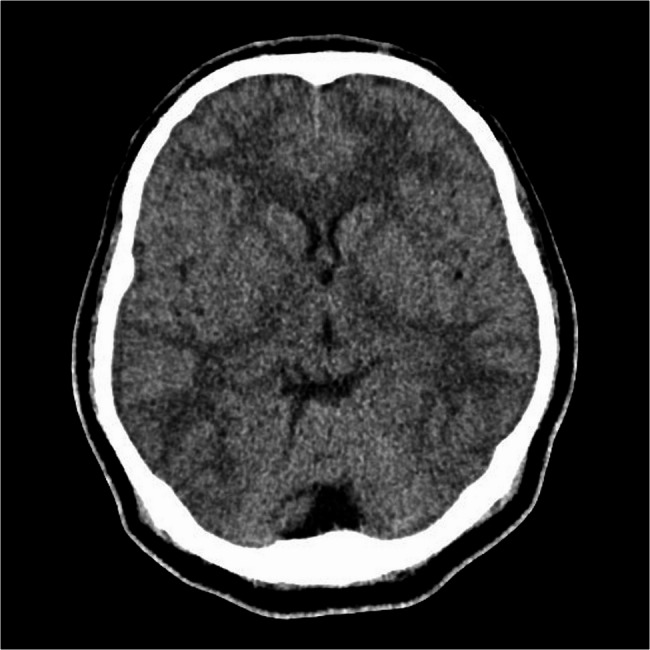

尽管在预防和治疗方面取得了进展,细菌性脑膜炎仍然是世界范围内发病率和死亡率的一个重要原因。及时诊断和适当的管理对患者的最佳预后至关重要。本病例报告描述了一名22岁的孟加拉国男性,因头痛、颈部疼痛、呕吐和左眼上睑下垂到急诊室就诊,最终被诊断为脑膜炎奈瑟菌脑膜炎。这个病例强调了罕见但重要的并发症动眼神经麻痹与这种感染有关。我们还发表了一篇文献综述,讨论了细菌性脑膜炎的发病率、病理生理学和脑神经受累的临床意义,重点是脑膜炎奈瑟菌,并探讨了细菌性脑膜炎和结核性脑膜炎重叠临床表现所带来的诊断挑战,特别是在资源有限的情况下。

Bacterial meningitis remains a significant cause of morbidity and mortality worldwide, despite advances in prevention and treatment. Prompt diagnosis and appropriate management are crucial for optimal patient outcomes. This case report describes a 22-year-old Bangladeshi male who presented to the emergency department with headache, neck pain, vomiting, and left eye ptosis, ultimately diagnosed with Neisseria meningitidis meningitis. This case highlights the rare but significant complication of oculomotor nerve palsy associated with this infection. We also present a literature review discussing the incidence, pathophysiology, and clinical implications of cranial nerve involvement in bacterial meningitis, focusing on N. meningitidis, and explore the diagnostic challenges posed by overlapping clinical presentations of bacterial and tuberculous meningitis, particularly in resource-limited settings.